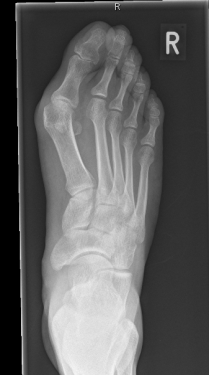

So, nun liege ich also hier, im St. Petrus-Krankenhaus zu Bonn, vor mir zwei Krücken (ja ich weiß, die Dinger heißen Unterarmgehstütze, aber es sagt ja auch kein Mensch ,Lichtzeichenverkehrsanlage‘), Jesus an der Wand – und der operierte Fuß, noch dick verbunden und mit einem gelblichen Zeug bepinselt, nur der Große Zeh und sein Nachbar schauen oben heraus. Dank einer besonderen Betäubung des rechten Beins verlief die Nacht ohne Probleme. Erst heute früh um kurz nach vier meldete er sich zurück, nicht direkt mit Schmerzen, eher mit einem Kribbeln, als ob er sagen wollte: „Hallo, da bin ich wieder!“ Morgen wird zum ersten Mal der Verband gewechselt, bin sehr gespannt, wie es geworden ist. Das erste Röntgenbild gestern sah schon sehr vielversprechend aus.

Von der OP bekam ich dennoch nicht viel mit, weil sie zum Glück hinter einem Sichtschutz ablief, ab und zu mal eine gut gelaunte Stimme und das Sirren der kleinen Motorsäge. Die Kiefer-OP vor sechs Jahren war viel viel schlimmer, vor allem schmerzhafter, DAS war Horror. Nach gut einer Stunde wurde mir – wie einer Entbundenen das Baby – das besagte Röntgenbild überreicht. Dann wurde ich erst in den Aufwachraum gebracht, wo nach wenigen Minuten das linke Bein erwachte, danach zurück ins Zimmer.

Vorher:

Rechts vorher